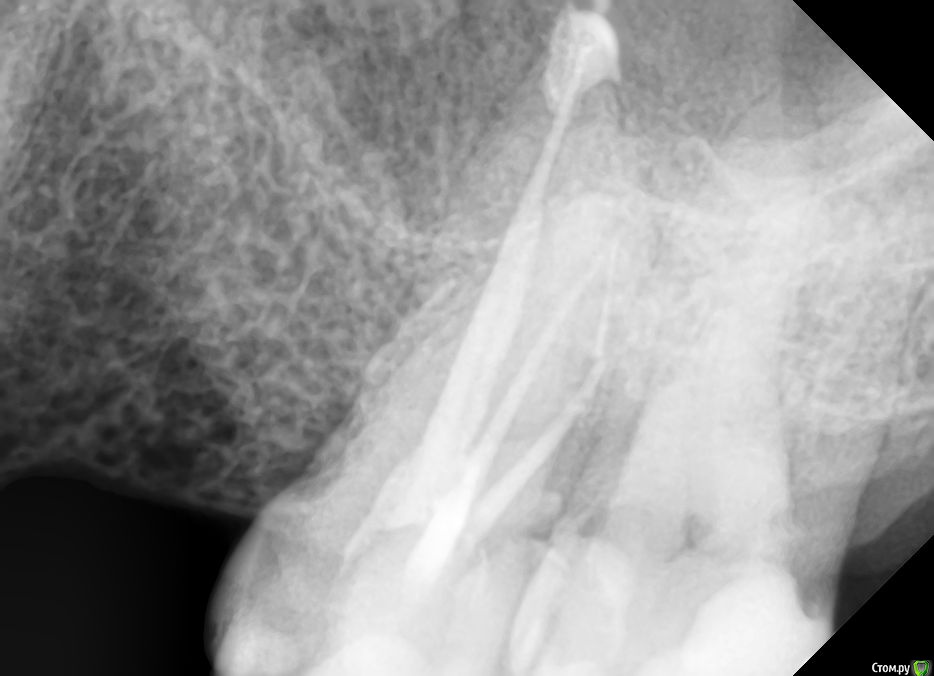

anvladd Опубликовано 3 января, 2017 Поделиться Опубликовано 3 января, 2017 Однозначно переделывать,в дистальном щечном канале сломанный инструмент. Ссылка на комментарий

DmitrySH Опубликовано 3 января, 2017 Поделиться Опубликовано 3 января, 2017 Инструмент в 6 зубе есть. Я бы сейчас не пытался достать, т.к. инструмент за изгибом корня и создание доступа потребует достаточно инвазивной работы. Нужно 7 зуб на витальность проверить. и сделать КТ на предмет еще одного канала в 6 зубе. Ссылка на комментарий

sugaka30 Опубликовано 4 января, 2017 Автор Поделиться Опубликовано 4 января, 2017 (изменено) Инструмент в 6 зубе есть. Я бы сейчас не пытался достать, т.к. инструмент за изгибом корня и создание доступа потребует достаточно инвазивной работы. Нужно 7 зуб на витальность проверить. и сделать КТ на предмет еще одного канала в 6 зубе. Спасибо за ответ ! 7 ка пломбированна делал недавно Эод результат 46 и 47 Горячее и холодное она не чувствует и нажим не болезненный По поводу 6 ки вчера только узнал что врач запломбировал канал дистально прищечный Форфенановой пастой Наверное понял что инструмент сломан или что не до конца его прошел Основной канал гутаперча НЕТЕРМОФИЛЬНАЯ с конасоном Может это форфенан дает такой эффект Изменено 4 января, 2017 пользователем sugaka30 Ссылка на комментарий